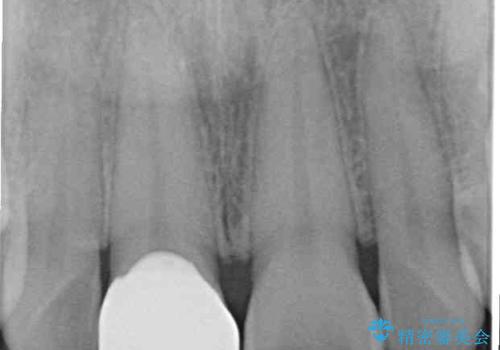

- 転んで欠けてしまった前歯を気にして来院された患者様です。

転んだ際に歯の先端1/4ほどが欠けてしまい、近医にて修復をしてもらったとのことですが、将来的にオールセラミッククラウンを装着する可能性を説明されたため、当院にて補綴治療を行うこととしました。